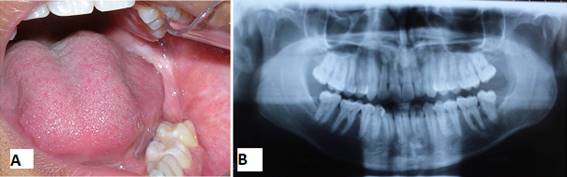

Paciente afrodescendiente, de sexo masculino, 17 años, estudiante, nacido en Fortaleza, estado de Ceará, en Brasil, que buscó atención en una clínica odontológica privada con quejas de supuración en la boca. Como nos informó la madre, durante aproximadamente un mes el paciente había sentido un mal sabor en la boca. Buscaron un cirujano dentista clínico que, al solicitar una radiografía panorámica de los maxilares, notó una lesión en la mandíbula y lo remitió al cuidado del cirujano bucomaxilofacial. En la anamnesis, no mencionó ninguna queja de dolor: solo mencionó mal sabor en la boca y mal aliento. En el examen físico extrabucal se observaron facies simétricas y ausencia de deformidades faciales. Cadenas ganglionares del complejo cervicofacial sin alteraciones. En el examen intrabucal era visible una supuración en la región del surco gingival lingual y distal 37. Elevación discreta en la región del trígono retromolar izquierdo con punto de fluctuación, de consistencia líquida. Examen de imagen (ortopantomografía) que muestra una extensa lesión osteolítica en la región del ángulo y rama ascendente mandibular izquierda, de aspecto expansivo, asociada al 38 incluido desplazado hacia el hueso basilar (Fig. 1).

Para una mejor evaluación de la extensión de la lesión, se solicitó una tomografía volumétrica de haz cónico de la región, donde se pudo observar sus límites y relaciones anatómicas circundantes (Fig. 2).

Un año después de la primera intervención, hubo una clínica y radiográficamente significativa reducción de la lesión (Figs 6 A y 6 B). Entonces se propuso realizar la enucleación de la cápsula remanente del quiste y de los elementos 38, 18, 28 y 48, bajo anestesia general.